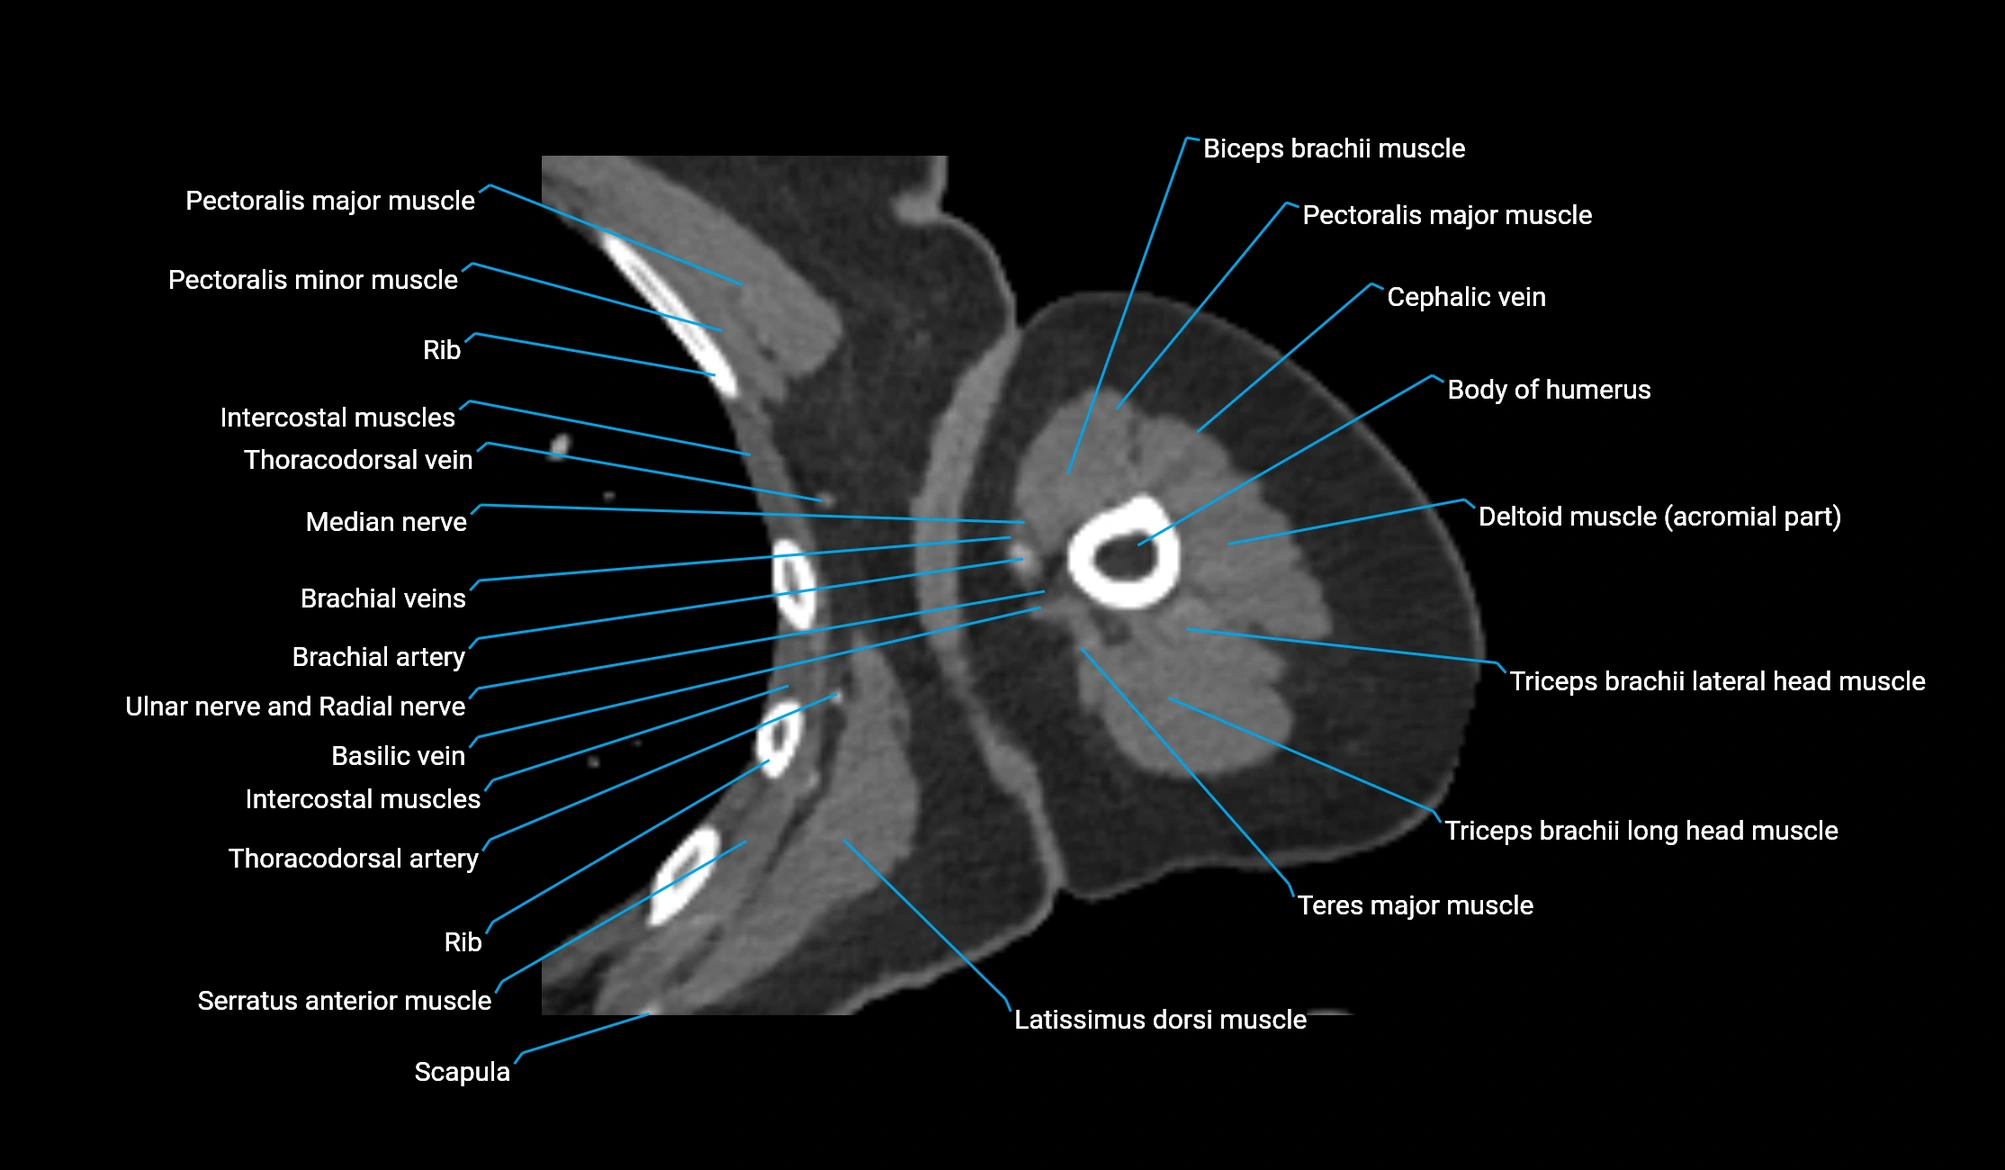

CT image